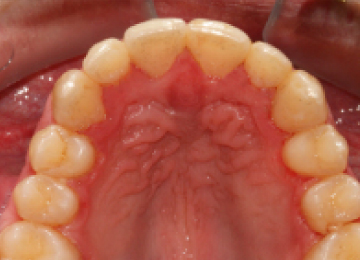

Брекеты Incognito: фото До и После

- Установка системы. Средний срок ношения систем 1,5 лет, согласно плану лечения и отслеживания результатов.

- Снятие брекетов, чистка зубов и процедура минерализации.

- Установка ретейнеров для завершения процесса исправления прикуса и выравнивания зубов.